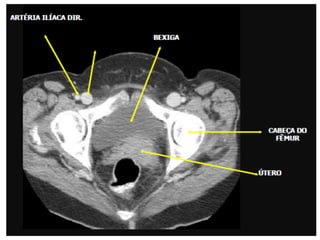

Varredura da Pelve

• Os limites são definidos pela extremidade

superior da crista ilíaca até a extremidade

inferior do ísquio.

• Os pacientes devem ser posicionados em

decúbito dorsal sem angulação do gantry.